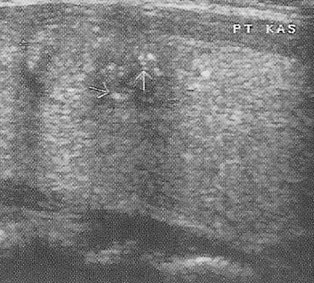

Ultrasonda tiroit kanser riski bulguları: Çapı 2.5-3cm'den büyük olan katı (Şekil 4) ya da karışık nodüller, çapı 4cm'den büyük kistik nodüller, kenarları düzensiz (Şekil 5) ve/veya içinde küçük kireçlenme odakları bulunan nodüller (Şekil 6), içinde ve etrafında kan akımı artmış olan nodüller ve izlemler sırasında büyüyen nodüller riskli nodüllerdir. Bunlardan bir kaçının beraber bulunması riski arttırır.

Fazla çalışan bir nodül (toksik nodül) varlığına da nodül ve çevresinde kan akımı artmış olabilir. Diğer yandan tiroitte yaygın olarak kan akımının fazla olduğunun saptanması, Graves hastalığı ya da Hashimoto hastalığı için bir gösterge olabilir (Şekil 7).

Şekil 4 ![]() | Şekil 5 ![]() | Şekil 6 ![]() | Şekil 7 ![]() |